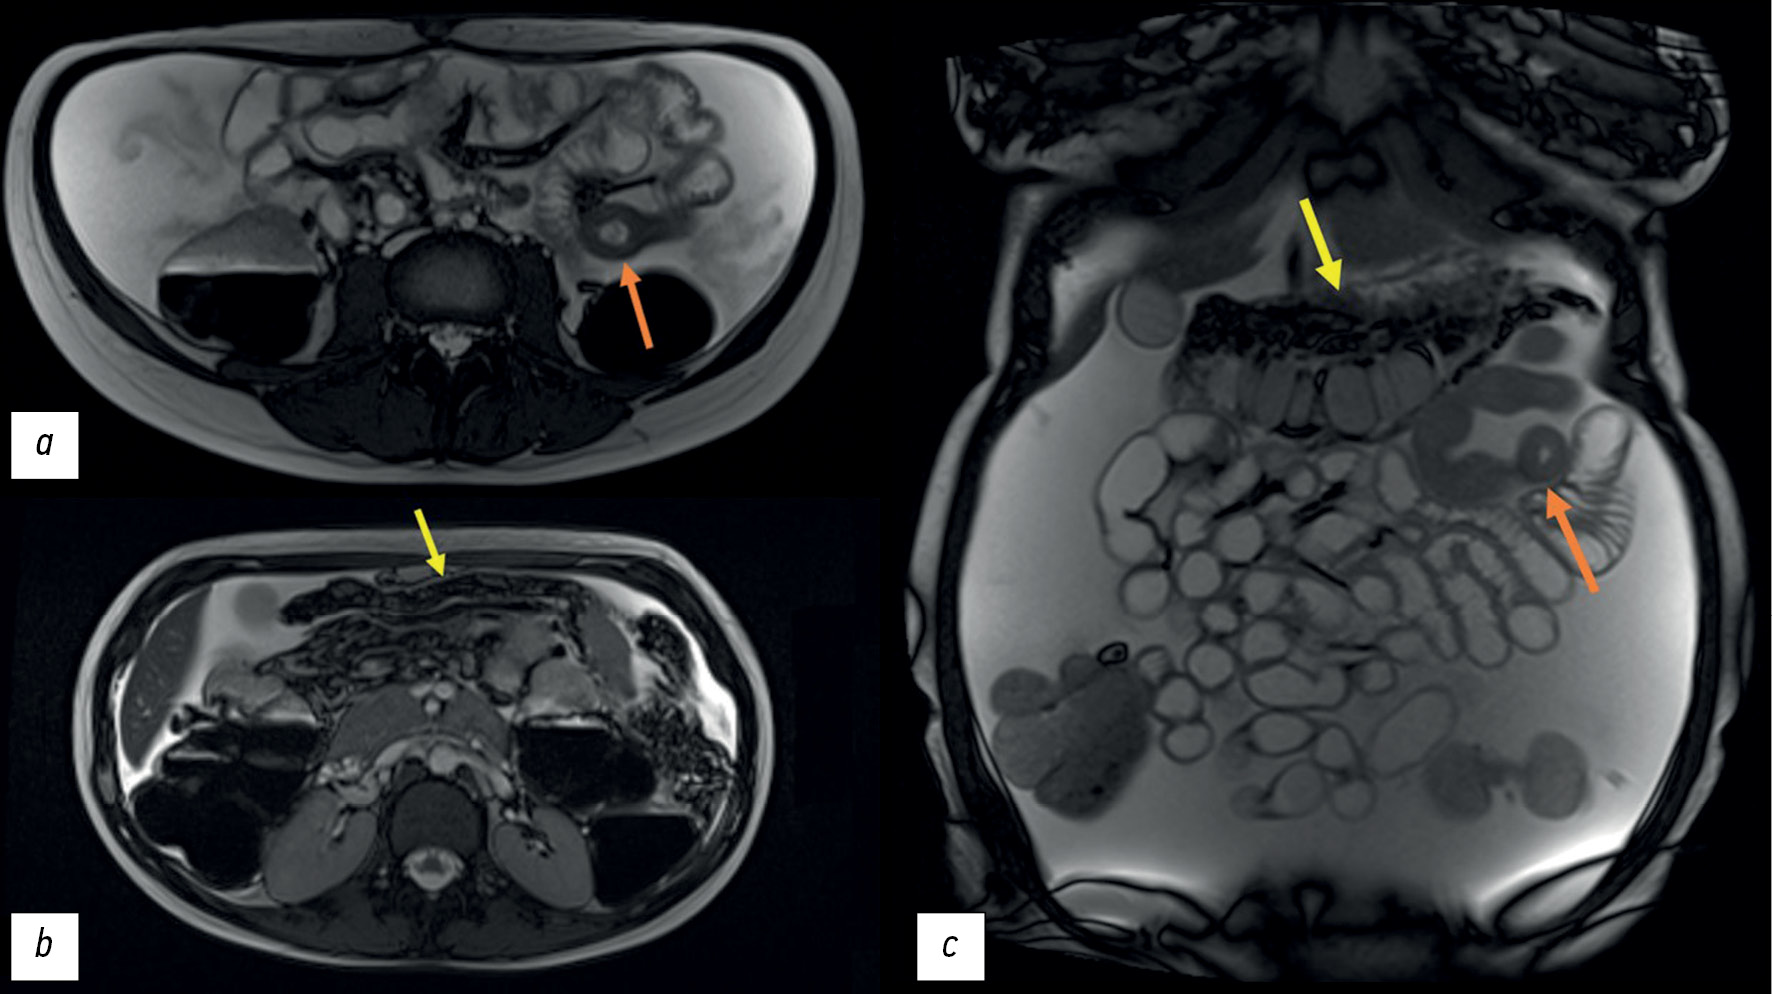

Given the history of conglomerate small and large bowel loops and intestinal symptoms, magnetic resonance (MR) enterography was performed, which showed circular homogeneous thickening of the wall and narrowing of the lumen of the first parts of the small intestine to 12 mm over approximately 50 cm with increased contrast enhancement. A “pie-shaped” infiltration of the greater omentum and a large amount of free fluid in the abdominal cavity was observed (Figure 3).

Fig. 3. Magnetic resonance imaging, T2-weighted images: a, b - axial plane; c — coronal plane; orange arrow—thickened wall of the jejunum; yellow arrow - compacted and thickened greater omentum.